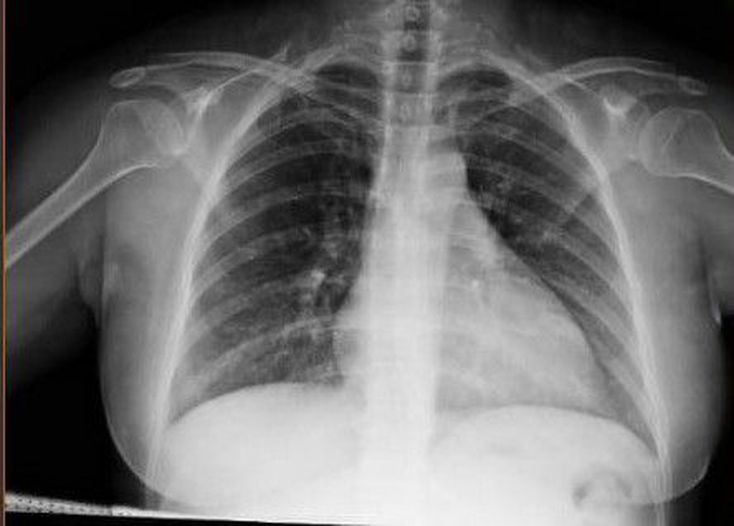

Guess the diagnosis?

Cardiomegaly

Pluera effusion

Tof